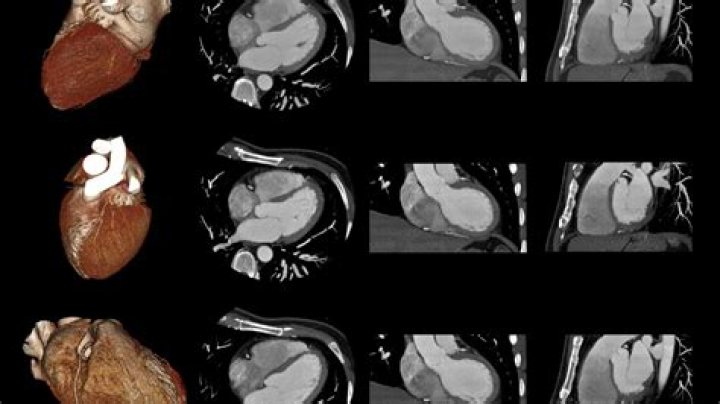

Which angiography is best?

Is CT coronary angiography better?

64-slice CT coronary angiography has a high negative predictive value (95% to 100%) in stable patients with low pretest probability of coronary artery disease. CT coronary angiography has comparable sensitivity and specificity to traditional catheter based invasive coronary angiography.

Results: The diagnostic accuracy of CT coronary angiography was evaluated regarding true positive, true negative values. The overall sensitivity and specificity of CT angiography technique was 100% (95% confidence interval [CI]: 39.76%–100%) and 91.30% (95% CI: 79.21%–97.58%).